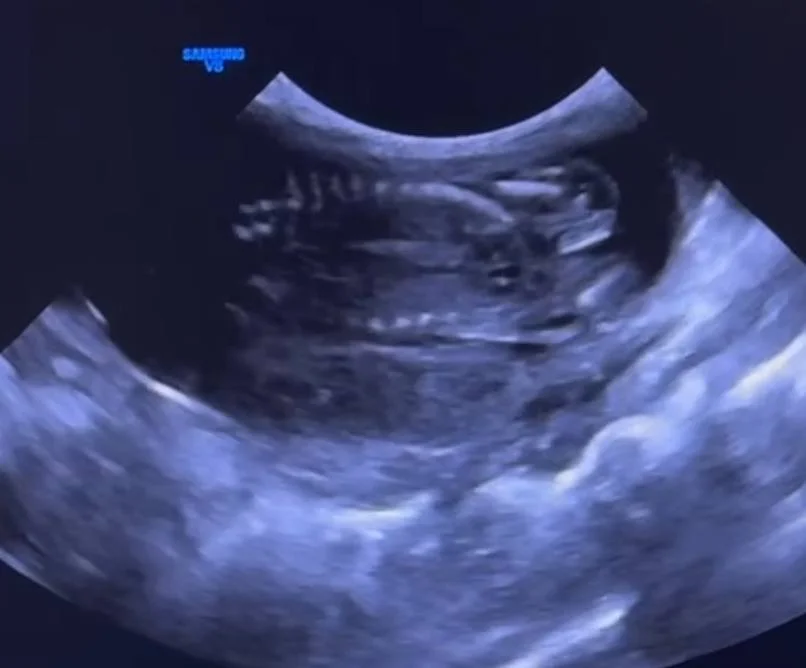

Это оказалась не опухоль, а беременность 😀

Скоро наша морская свинка станет мамой :)

Так что купили мы 4х морских свинок по цене одной 😂